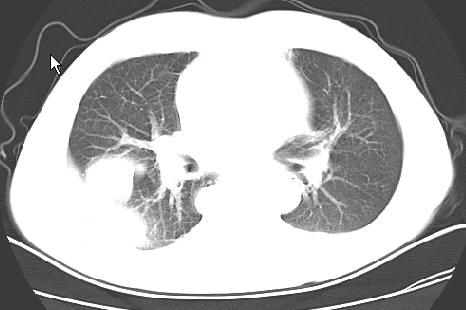

以下是引用草之原在2009-5-2 19:29:00的发言:[br]1.考虑右侧中心型肺ca纵膈淋巴结转移,双侧胸腔积液及右侧叶间裂积液,心包积液。[br]2.两肺上叶病灶,纵膈窗显示部分病灶硬化,考虑:结核。[br][br] [br]

以下是引用ct诊断高手在2009-5-2 19:08:00的发言:[br]我考虑右侧中央型肺癌 伴右肺节段性不张,两肺及纵隔淋巴结转移,右侧胸腔积液。

以下是引用zjzjr在2009-5-2 20:16:00的发言:[br]肺结核,转移瘤.纵隔淋巴结转移或淋巴瘤,右侧包裹性积液、斜裂积液。心包积液。